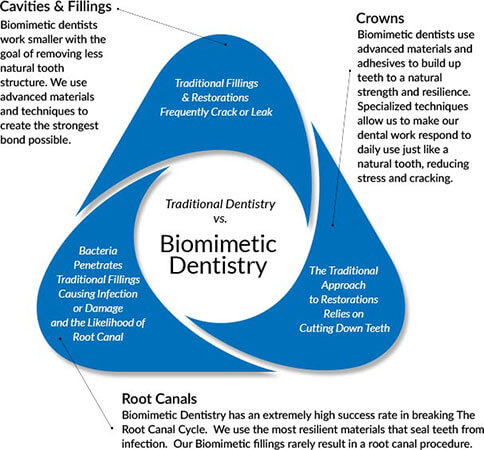

Biomimetic Dentistry | St. Lawrence

East Lake Advancing Dentistry :: Andrey Eng, DDS :: Biomimetic

Biomimetic/Cosmetic Dentistry | IDSLI - Holistic Dentistry